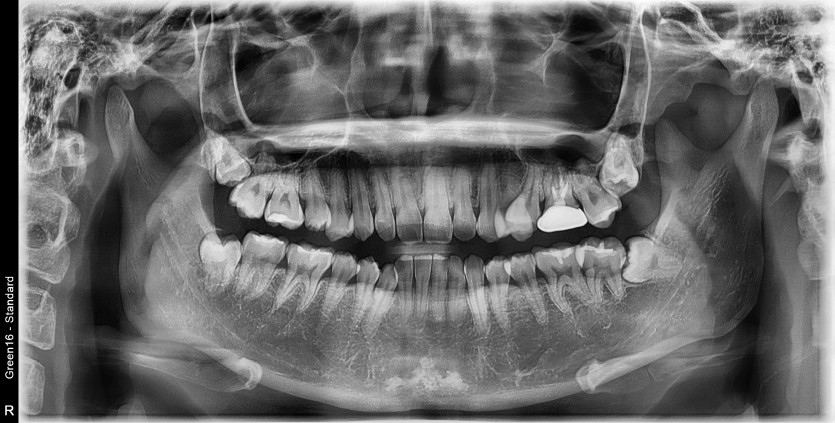

#18,48 사랑니 발치

구강 외과 전문의가 당일 발치했습니다.